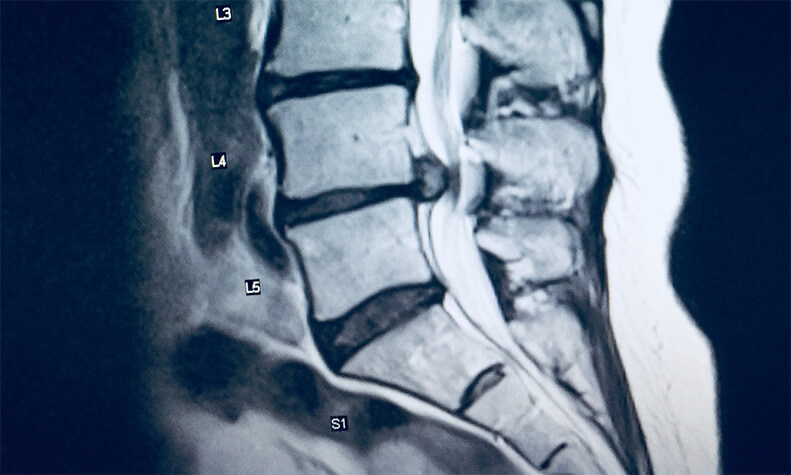

The plaintiff had a long history of back pain. In July 2016 she underwent an MRI which showed some disc disease at both L4-5 and L5-S1. There was also a large central disc extrusion slightly narrowing the thecal sac and impinging on the descending right S1 nerve root.

Five hours after being discharged the plaintiff returned again via ambulance to the emergency department in severe pain. The ER physician on this visit ordered an immediate MRI of her spine which showed large disc herniations pressing on the nerves in her lower back. The plaintiff was diagnosed with cauda equina syndrome. Neurosurgery was contacted and the plaintiff underwent emergency surgery to relieve the pressure on her nerves.